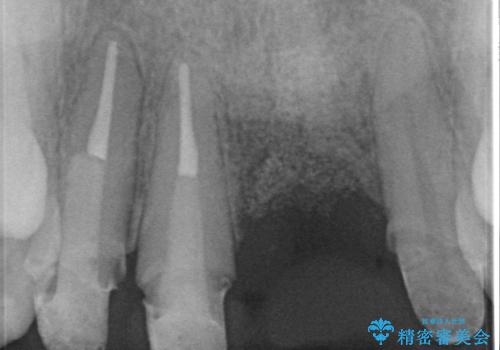

左側の前歯には他院で埋入されたポジションの悪いインプラント補綴により歯冠長の長いクラウンが装着されており、感染による排膿も認められこのまま審美性を改善するのは難しい状態です。

感染したインプラントからは排膿が間欠的に認められ、掻爬・除去が検討されうるような状況でした。